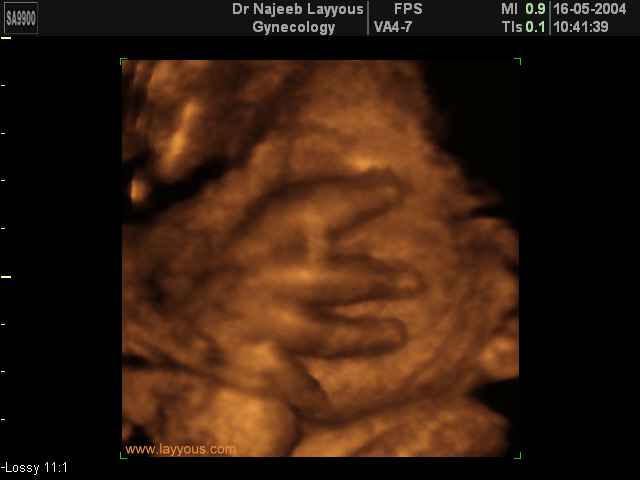

- 3D Fetal Limbs Ultrasound Scan Photos

3D Ultrasound Scan Photos of Fetal Limbs | Dr N Layyous